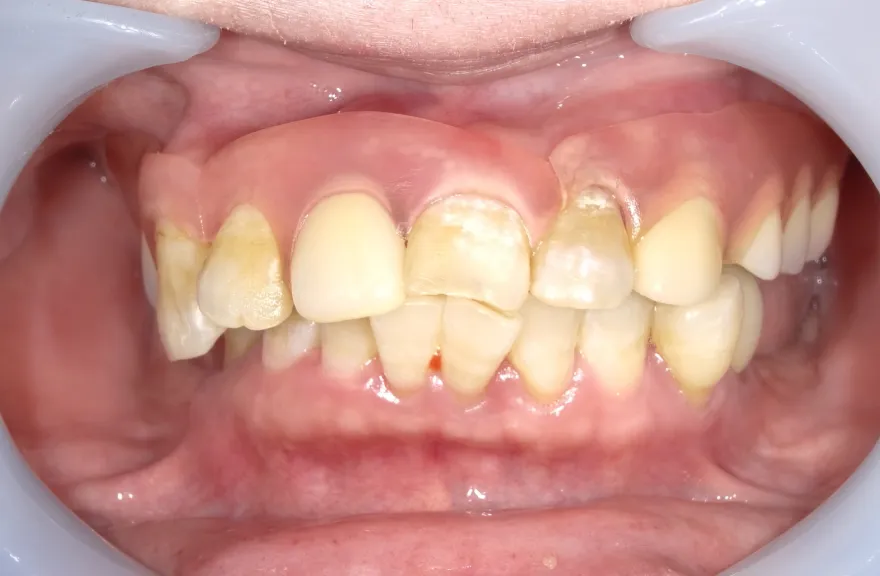

【治療例 2】金属を白くしたい63歳

- 相談内容

-

右上の奥歯が取れたということで来院されました。

各所の金属は昔に治療されたもので、外してみるとどれも虫歯になっていました。

一つずつ虫歯治療を行い、インプラント治療、矯正治療を並行して行いました。 - 治療費用・方針

写真の通りに治療を終了いたしました。

各所虫歯に侵食されていましたが、歯を残すことができたのでインプラントの数をおさえることができました。

下の前歯が先天的に1本欠損しており、そのため噛み合わせを構築することが難しいケースでした。矯正治療を併用することで前歯と奥歯をバランスよく噛ませることに成功しました。